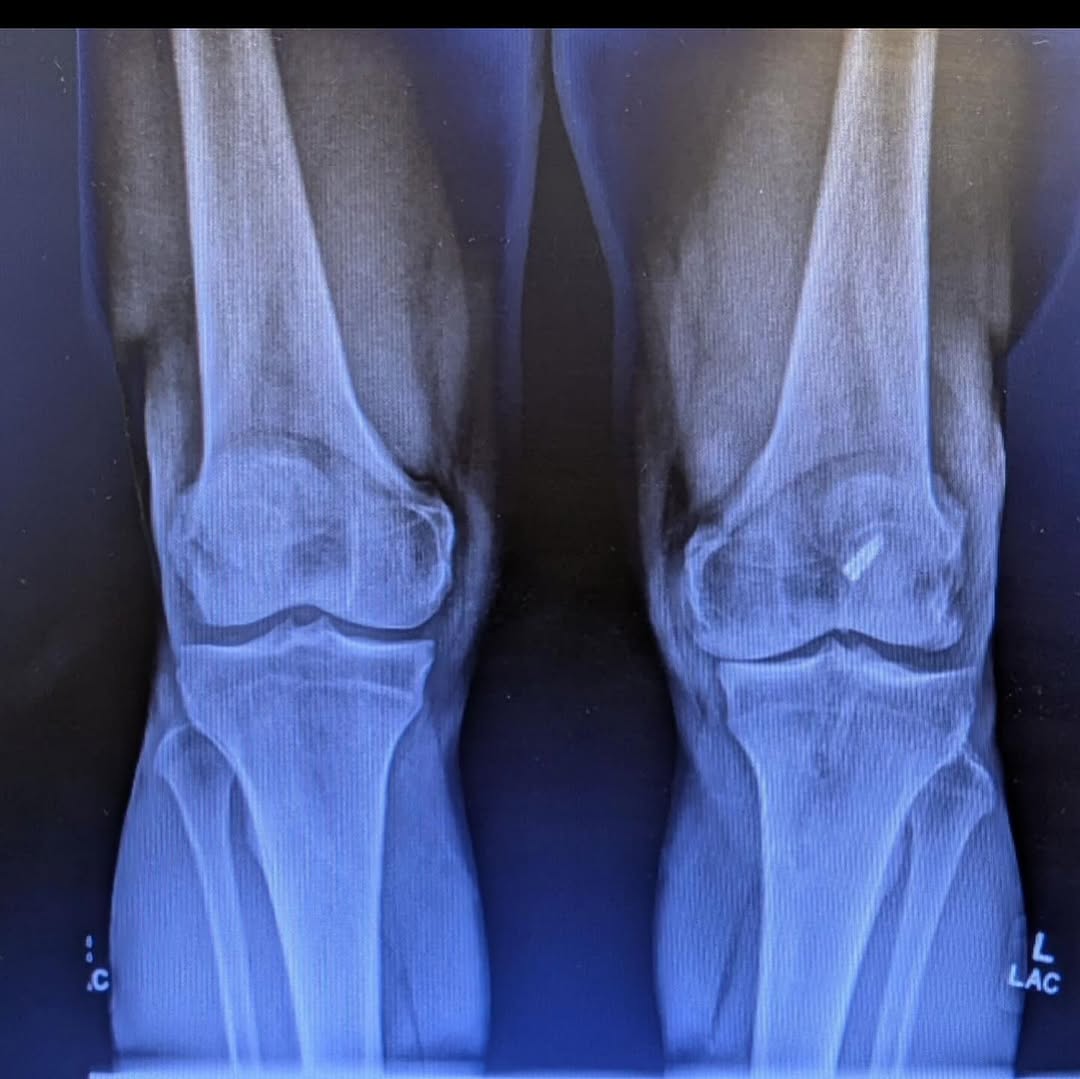

“How it was. And how it is…

I am 7 weeks post op on a Total Knee Replacement. My left knee was on its last leg, and I have been putting this surgery off for years. Post op X-Rays show everything is healing nicely. Many thanks to Dr. Nicholas Dirig, Derek Bobst, and their excellent team for my surgery. Thanks to Bill Wall of Physical Therapy Specialist for getting me back on track.